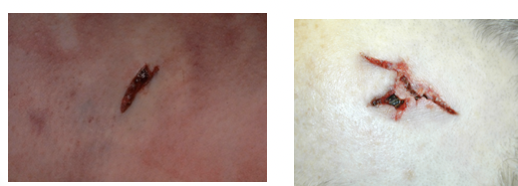

List the important factors to document for stab wound injuries (6)

irregular defect whose edges can be re-approximated

stellate, beveled, slit, crescent

everted margins

no marginal abrasion, but can be shored (collar of abrasion)

exit wound

entry wound

exit wound

incised wound

clean, cut edges, well-defined, free from contusions

spindle-shaped

lots of hemorrhage from clean cut vessels

deeper at the beginning and more shallow at the end (“tailing”)

stab wound

depth > length

width of wound < width of weapon - stretching of skin

clean cut edges

punctures around concealed parts of the body (axilla, vagina, rectum, nostrils)

removing the tension caused by the elastic fibers in the skin is necessary to evaluate the true shape

isolating the area by cutting it from the surrounding skin and subcutis or with transparent tape

describe the procedure necessary to evaluate the true shape of a stab wound